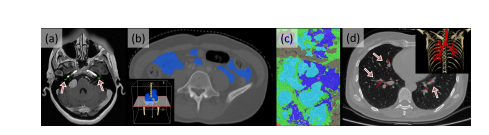

Fig. 4: Typical examples of meeting the exclusion criteria. (a) cochlea (criteria1), (b) intestine (criteria 2), (c) histopathological breast cancer (criteria 3), and (d) lung trachea trees (criteria 3). The corners (b) and (d) show the 3D rendering images obtained by Pair annotation software package (Liang et al., 2022).

图4:典型的符合排除标准的例子。(a) 耳蜗(标准1),(b) 肠(标准2),(c) 组织病理学乳腺癌(标准3),以及(d) 肺气管树(标准3)。角落(b)和(d)展示了通过Pair注释软件包(Liang et al., 2022)获得的3D渲染图像。